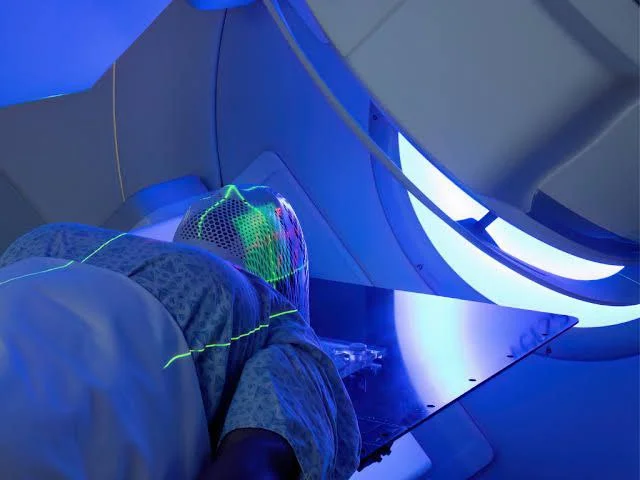

عوارض دهانی رادیوتراپی

مقدمه رادیوتراپی یکی از روشهای مؤثر درمان سرطان است که با استفاده از اشعههای یونیزهکننده به هدف از بین بردن سلولهای سرطانی و جلوگیری از رشد آنها انجام میشود. این روش، بهویژه در درمان سرطانهای سر و گردن، سینه و سایر نواحی بدن، کاربرد دارد؛ بااینحال، رادیوتراپی میتواند عوارض جانبی متعددی به همراه داشته باشد […]